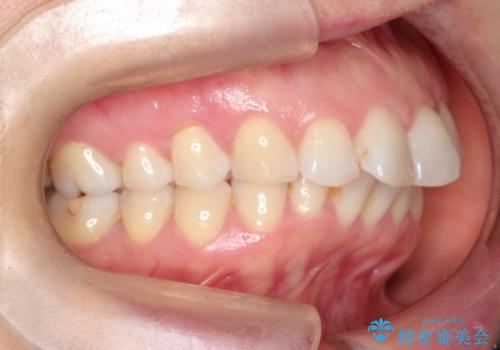

審美装置を用いたワイヤー矯正|非抜歯で歯の凸凹を改善

- 患者様は**歯の凸凹(叢生)**を気にされて来院されました。診査の結果、歯列のスペースが不足しているものの、抜歯をせずに改善できる状態でした。そこで、目立ちにくい審美装置(白いブラケットとホワイトワイヤー)を使用したワイヤー矯正を提案しました。歯列のアーチを広げながら、適宜IPR(歯の幅をわずかに調整する処置)を行い、非抜歯で自然な歯並びへと導く計画を立てました。

治療では、白いブラケットとホワイトワイヤーを使用し、矯正装置が目立ちにくいよう配慮しました。歯列を拡大しながら適切に歯を移動させ、IPRを併用することで、無理なくスペースを確保しました。見た目に配慮しながら、歯の凸凹をスムーズに整え、噛み合わせも改善。患者様からは「装置が思ったより目立たず、歯並びがきれいになって嬉しい」との声をいただきました。